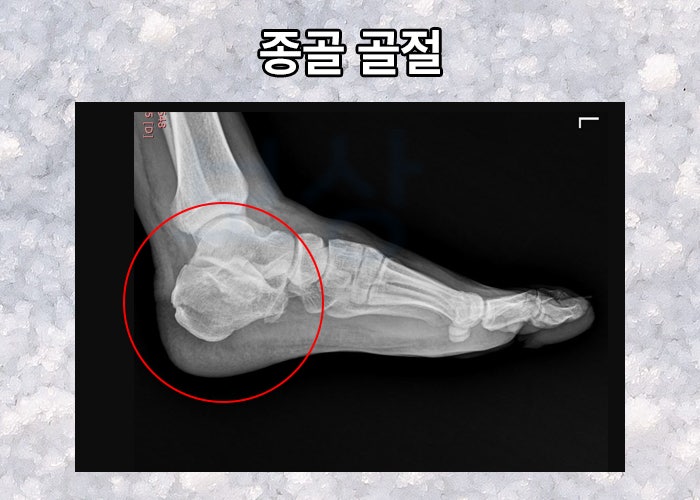

근족막염, 종골 골절 수술 받은 적 있다면 받아야 할 보상은?

주치의가 수술 자체에는 문제가 없기에 수술을 잘 되었다고 말씀했을 수 있습니다. 하지만 종골의 골절은 대다수 높은 곳에서 추락하며 발생하기에

발 바닥의 피부, 근육 조직이 손상되며

뼈 뿐만 아니라 관절면까지 손상되었을 수 있죠.

수술이 잘 되었다고 해도 정밀하게 설계되어 있던 신체를 원래의 상태로 되돌리기엔 정말 어려운 일입니다. 따라서 종골 골절 수술 후 발바닥의 통증이 생기고 걷기 힘들다면 이 보상을 알아봐야 하는데요,